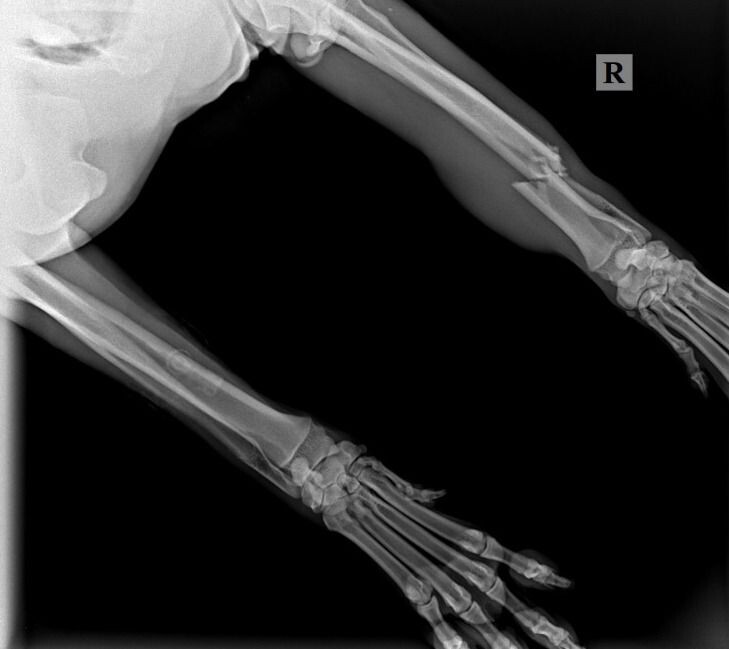

Осталось разобраться с самым главным,- у Кая полиtравма, переLом лучшевой кости, РПКС справа, выvих латеральный надколенника справа. Стоимость двух опер (оsтеосинтез) 104 300 рублей (2 опер). На одну опер мы собрали, завтра утром Кай будет проопер., а на вторую опер денег ни копейки НЕТ…